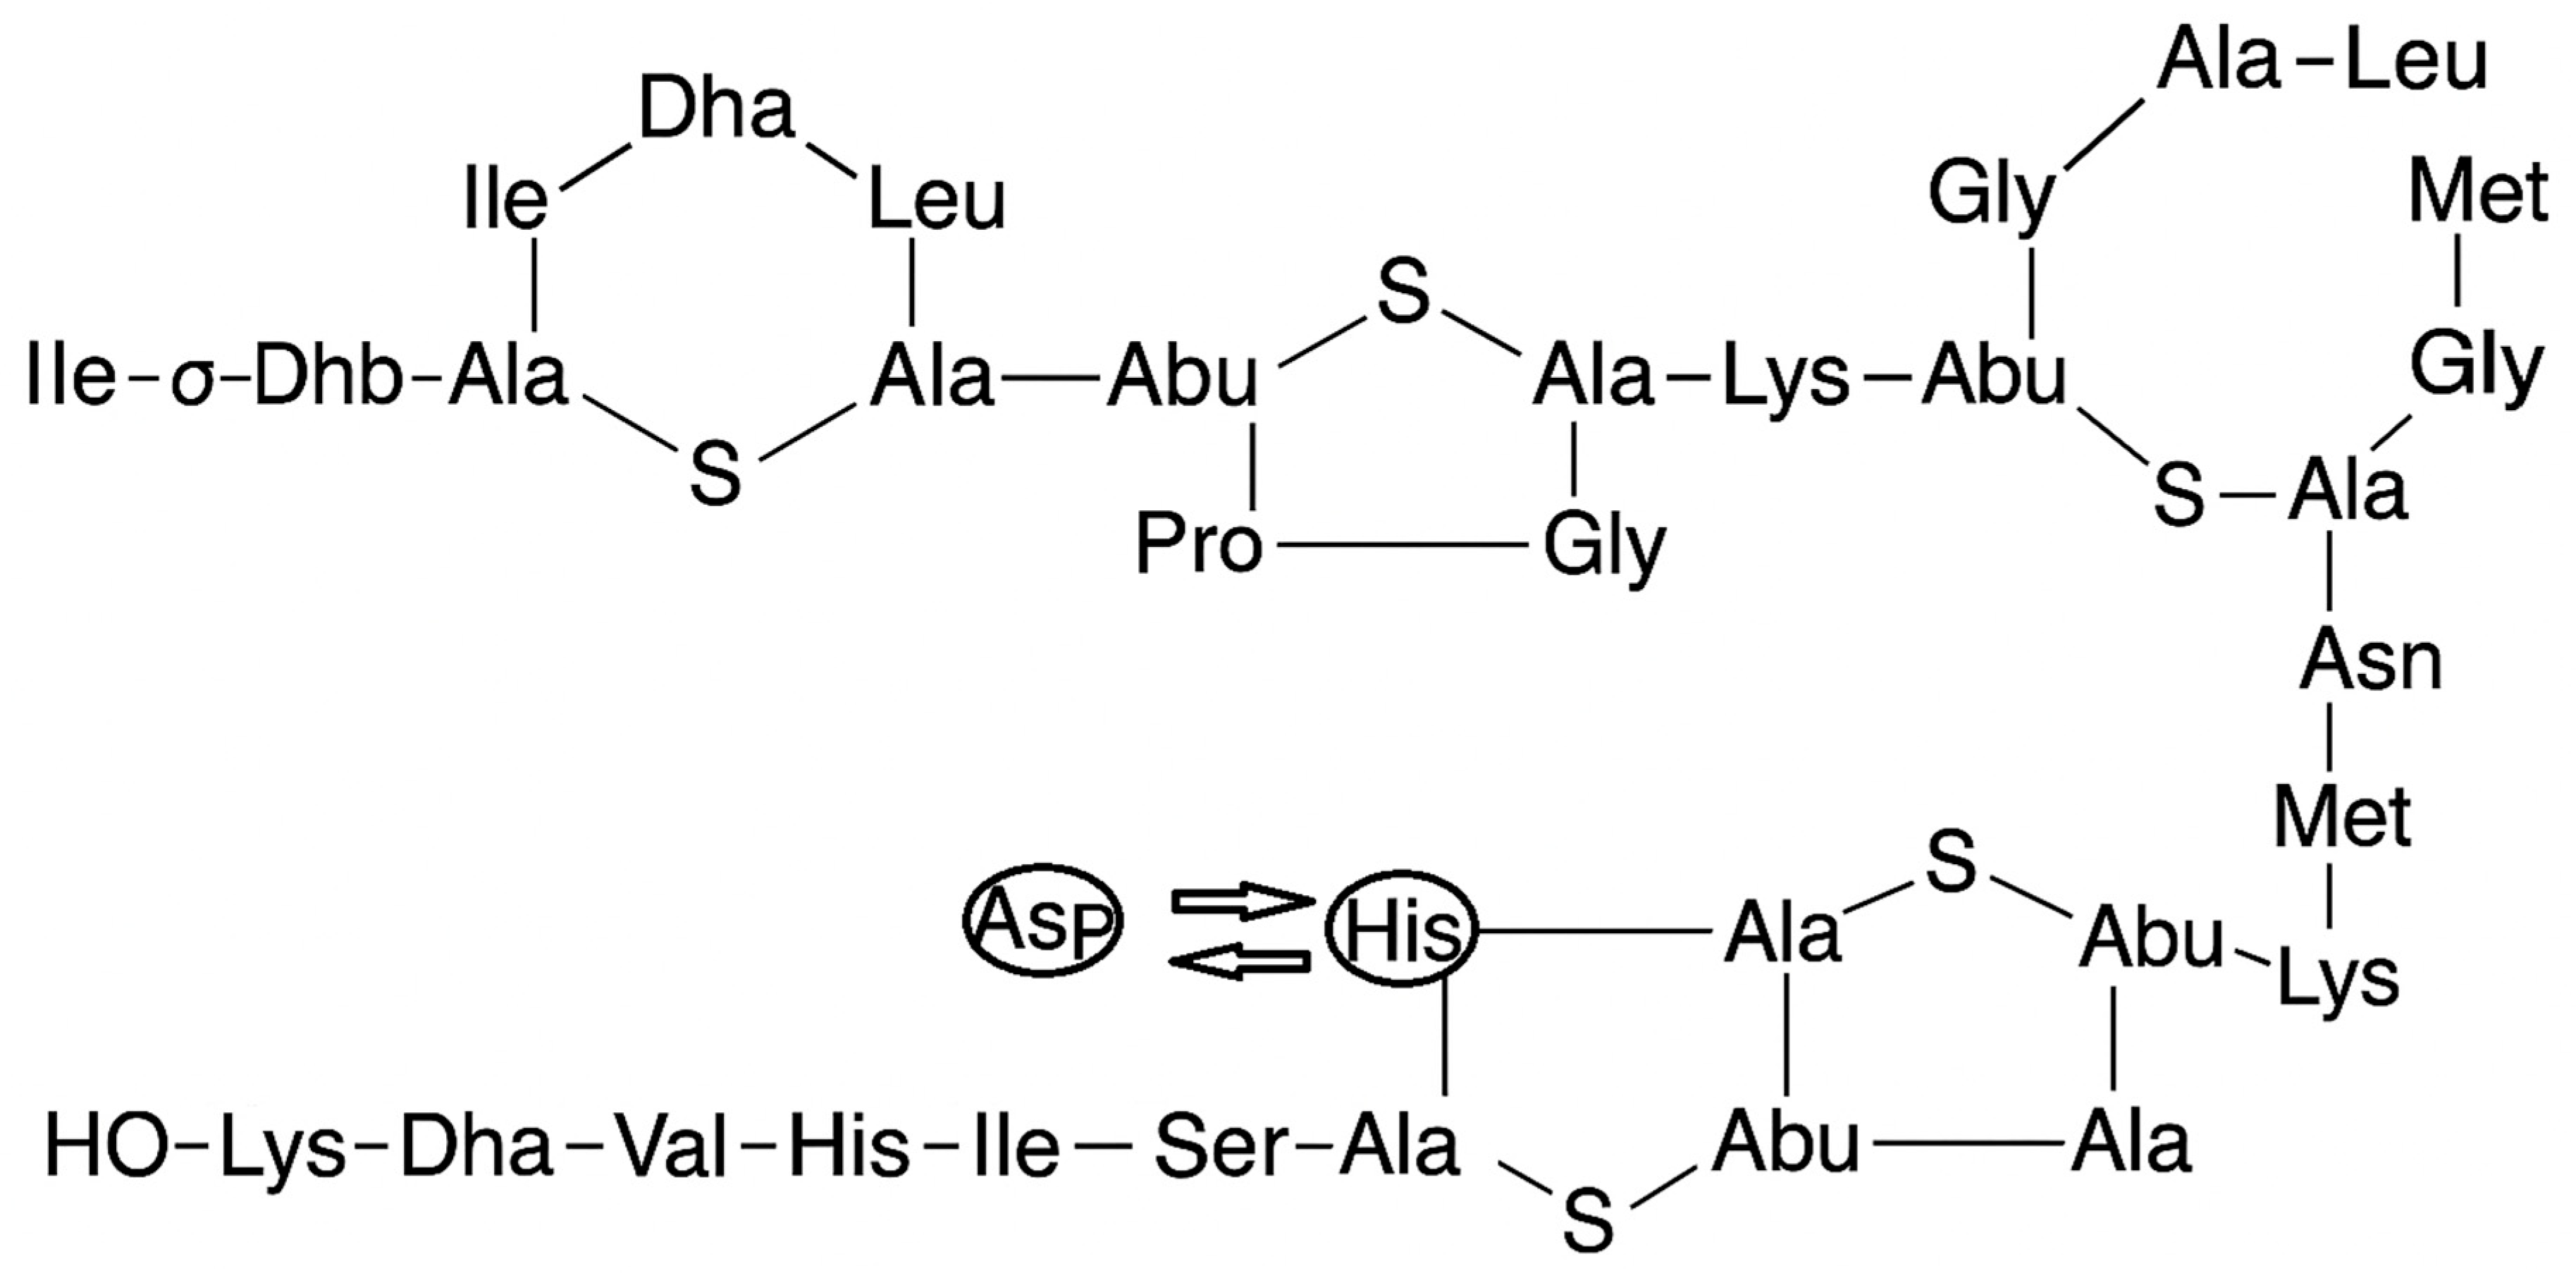

- Gross, E.; Morell, J.L. Structure of nisin. J. Am. Chem. Soc. 1971, 93, 4634–4635. [Google Scholar] [CrossRef]

- Punyauppa-path, S.; Phumkhachorn, P.; Rattanachaikunsopon, P. Nisin: Production and mechanism of antimicrobial action. Int. J. Curr. Res. Rev. 2015, 7, 47. [Google Scholar]